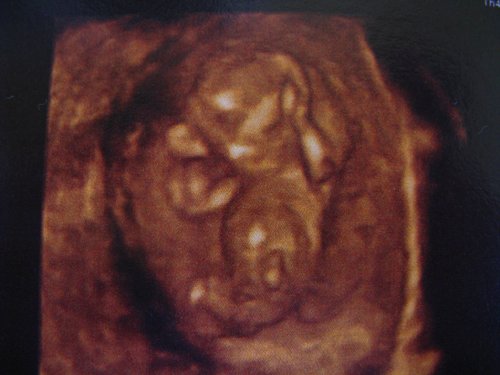

jaj de édes, tényleg nagyon formás a baba, ahogy a nagykönyvben mutatják. Tényleg log vmi a lába között, bár azt mondják, ilyenkor a csiklo is kiáll még.